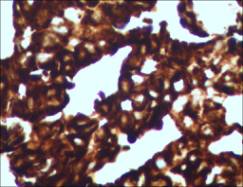

图示:腹水沉渣包埋发现腺癌细胞团TTF-1灶+,ALK融合蛋白阳性

病理活检(B1513618)示:(子宫内膜)形态及免疫组化符合:低分化腺癌伴局灶性鳞状分化,免疫组化TTF-1+、NapsinA+提示:肺癌转移而来。免疫组化:CK+,Vim-,P63灶+,CK5/6灶+,CK7+,CK18,CEA+,CA125+,Ki-67+80%,TTF-1+,NapsinA+,ER-,PR-,P53+70%。